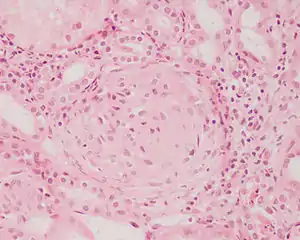

Rapidly progressive glomerulonephritis

Rapidly progressive glomerulonephritis, also known as crescentic GN, is characterised by a rapid, progressive deterioration in kidney function. People with rapidly progressive glomerulonephritis may present with a nephritic syndrome. In management, steroid therapy is sometimes used, although the prognosis remains poor.[9] Three main subtypes are recognised:[4]:557–558

Histopathologically, the majority of glomeruli present "crescents". Formation of crescents is initiated by passage of fibrin into the Bowman space as a result of increased permeability of glomerular basement membrane. Fibrin stimulates the proliferation of endothelial cells of Bowman capsule, and an influx of monocytes. Rapid growing and fibrosis of crescents compresses the capillary loops and decreases the Bowman space, which leads to kidney failure within weeks or months.